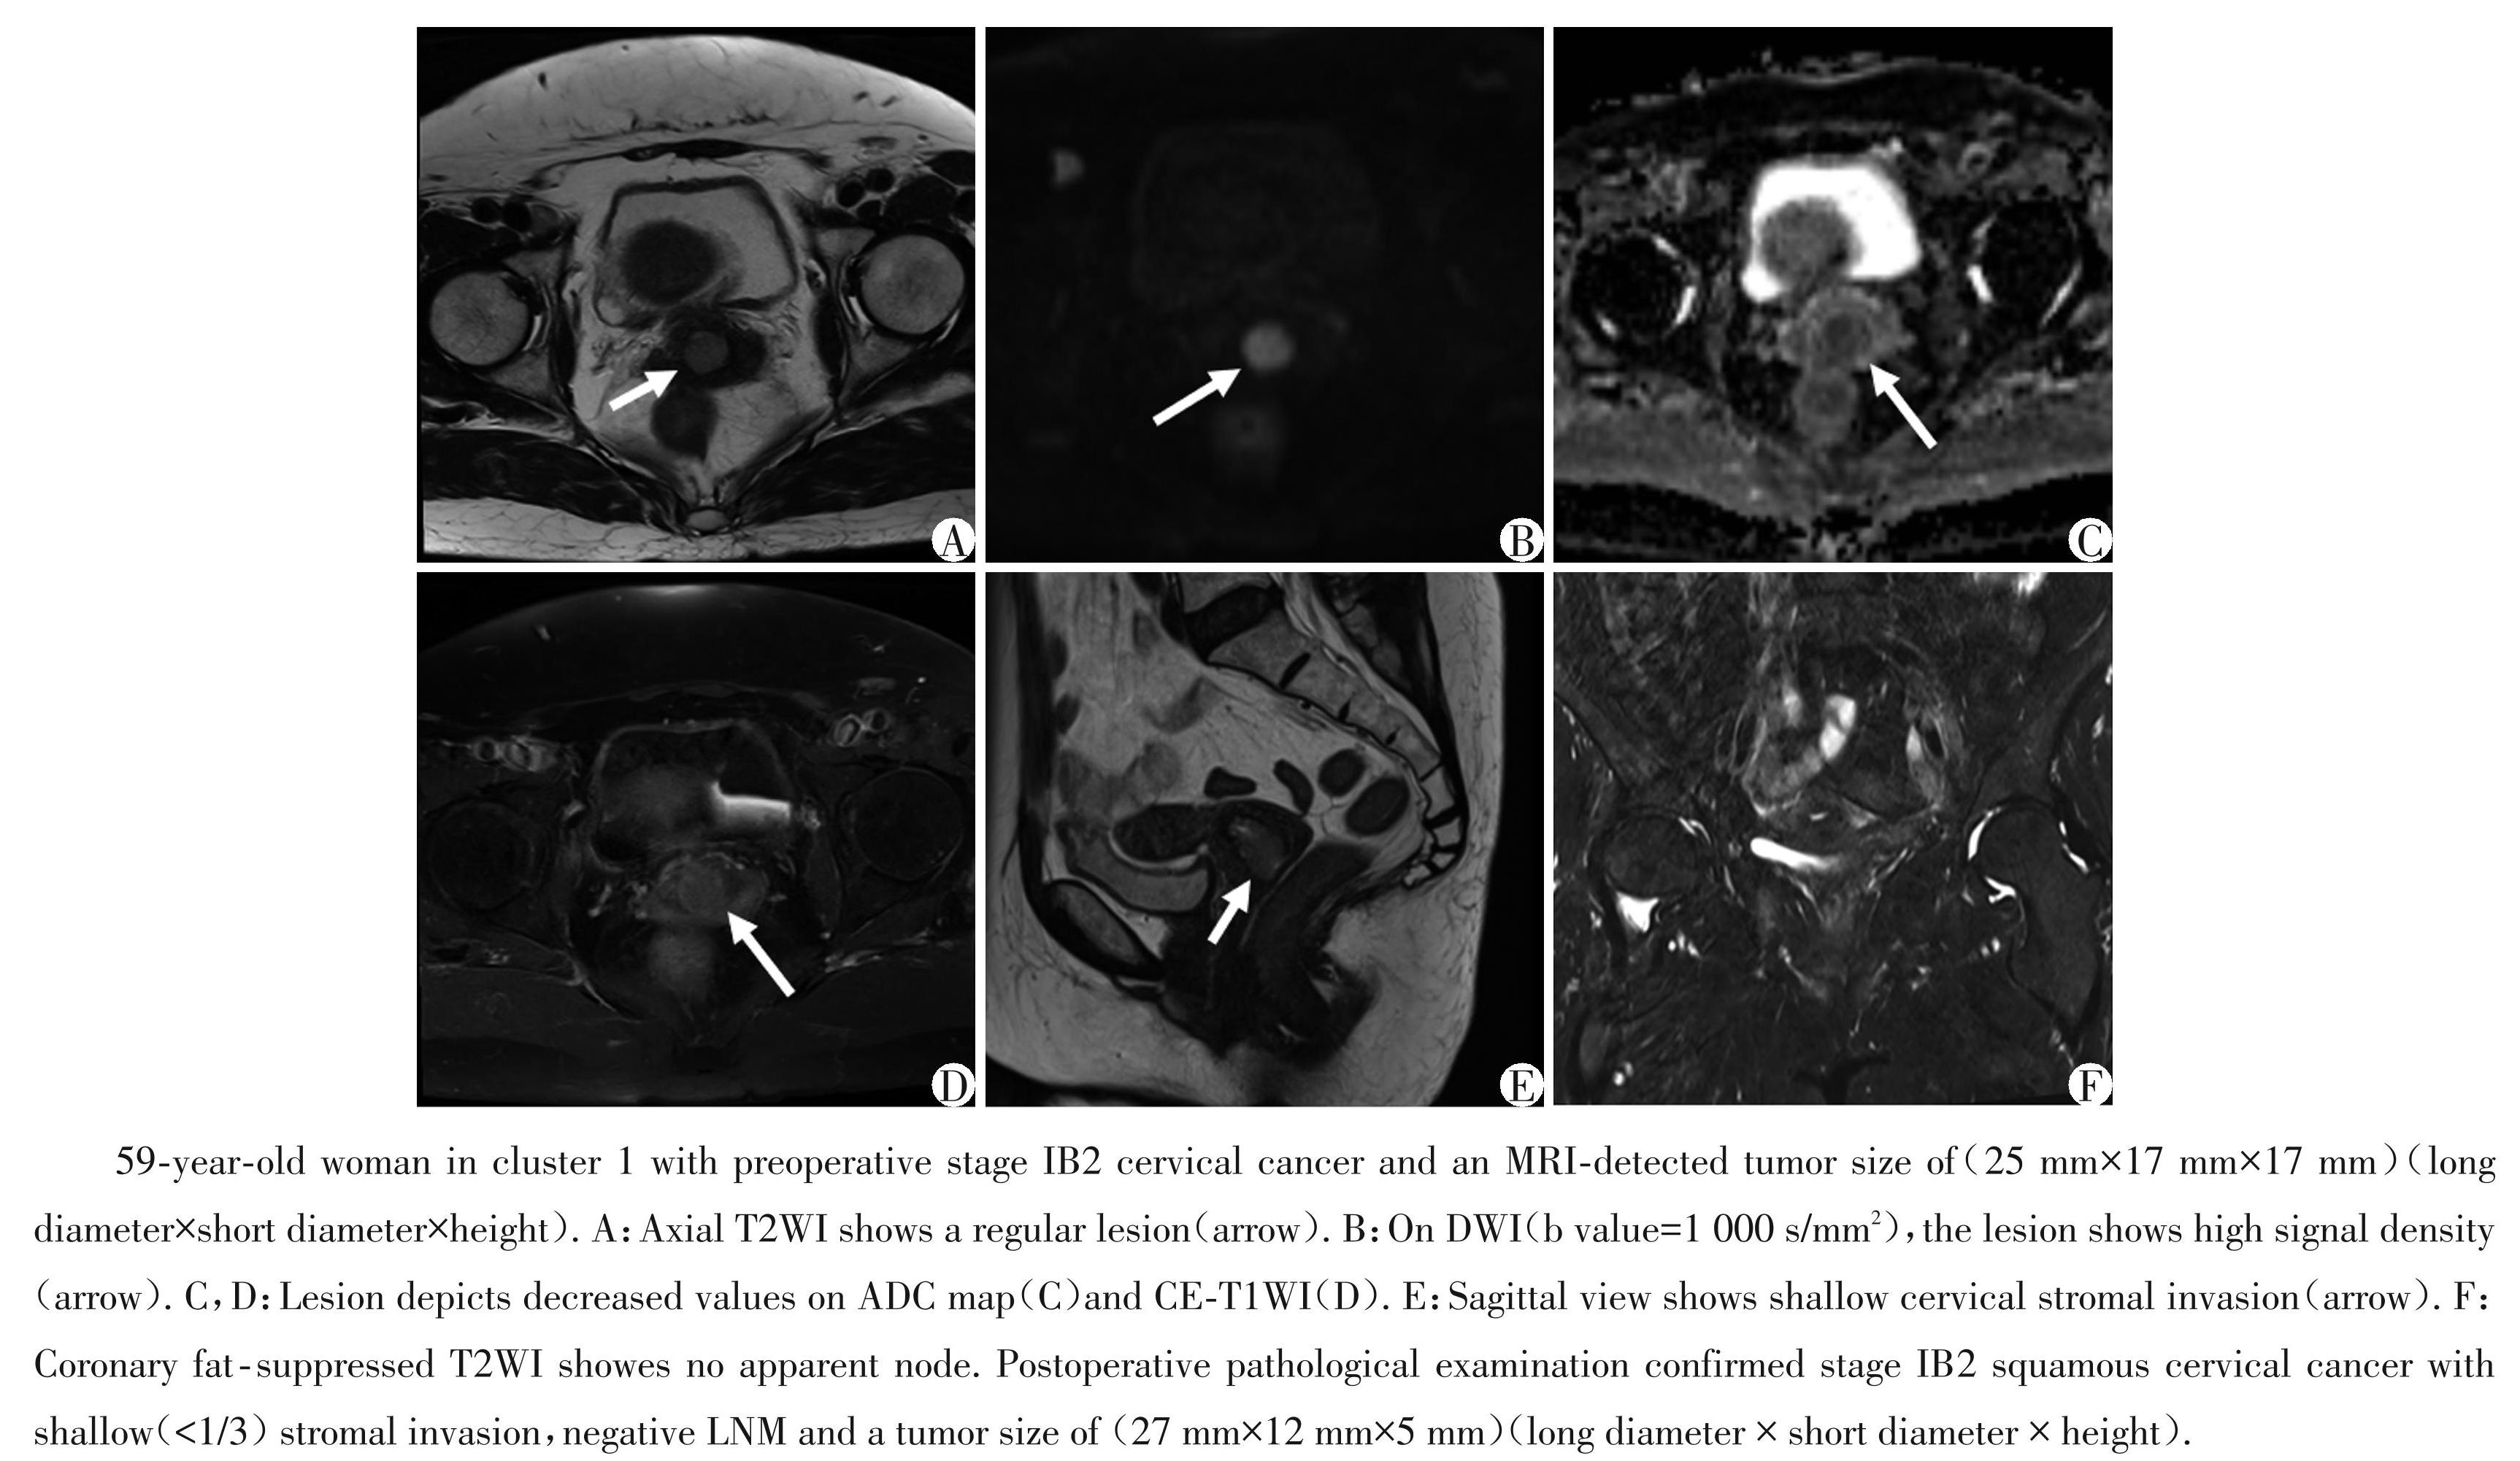

图3组1中的肿瘤具有较低临床及组织病理高危因素的典型病例

Figure3Typical case of a tumor in cluster 1 with lower risk clinical and histopathological high⁃risk factors

根据聚类预测指数和差距统计量,选择k=2作为最佳聚类数,最终将患者分为两组。表2总结了基于肿瘤的聚类分析结果以及两组间临床及组织病理学特征比较。结果显示,组 1 和组 2 之间在年龄(P=0.450)、组织学类型(P=0.665)、肿瘤分化程度 (P=0.440)、淋巴血管间隙侵犯(P=0.583)以及宫旁浸润(P=0.794)方面无统计学差异。组2的92例患者的 FIGO 分期晚于组 1,其中 Ⅲ Cp 期 30 例 (32.6%),ⅡB期1例(1.1%),ⅡA期25例(27.2%),而组1的患者大多为ⅠB期[50/72(69.4%)vs.36/92 (39.1%),P=0.001]。组2患者中30例(32.6%)存在盆腔淋巴结转移,这与FIGO ⅢCp期的患者数量相同,因为根据2018 FIGO指南,术后病理学证实存在盆腔淋巴结转移的患者被归为ⅢCp期,而组 1中只有9例(12.5%)淋巴结转移的患者,差异有统计学意义(P=0.002)。组2患者的肿瘤直径也明显大于组1 [短径:(28.38 ± 9.73)mm vs.(16.67 ± 6.32)mm,长径:(34.34 ± 9.72)mm vs.(21.02 ± 7.39)mm,高度: (29.92 ± 10.61)mm vs.(18.93 ± 8.01)mm,P 均 <0.001]。对于间质浸润深度,组 2 中宫颈间质浸润超过全层2/3的比例率明显高于组1[62/92(67.4%) vs.26/72(36.1%),P <0.001]。相比之下,组1中间质浸润深度在全层1/3~2/3以及<全层2/3的概率高于组 2[<1/3:13/72(18.1%)vs.10/92(10.9%):1/3~2/3: 33/72(45.8%)vs.20/92(21.7%),P 均<0.001]。图3和图4分别展示了每组的一个典型病例。